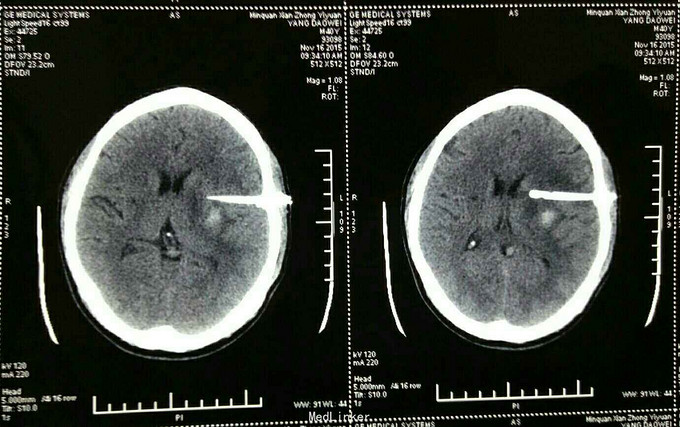

杨XX,男,40岁。 主诉:右侧上下肢无力伴失语15天。 病史:15天前在浙江务工时突然晕倒,随到浙江台州某医院就诊。神志清,精神差,查头颅CT示:“脑出血”,给予保守治疗。15天后家属要求转入原籍我院治疗。转入院时:神志清,精神可,血压:164/98mmHg,失语,右侧上下肢瘫痪,右侧上下肢肌力0级。 既往未检测血压。

诊断:高血压脑出血 治疗:微创钻孔血肿引流术。 术后应用尿激酶溶解血肿,引流顺利。 术后第四天拔除引流管。